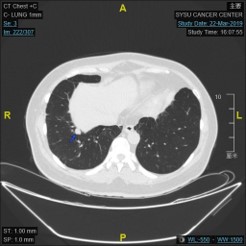

2019.3.22:

基线:

2程后SD:

4程后PR:

6程后PR: